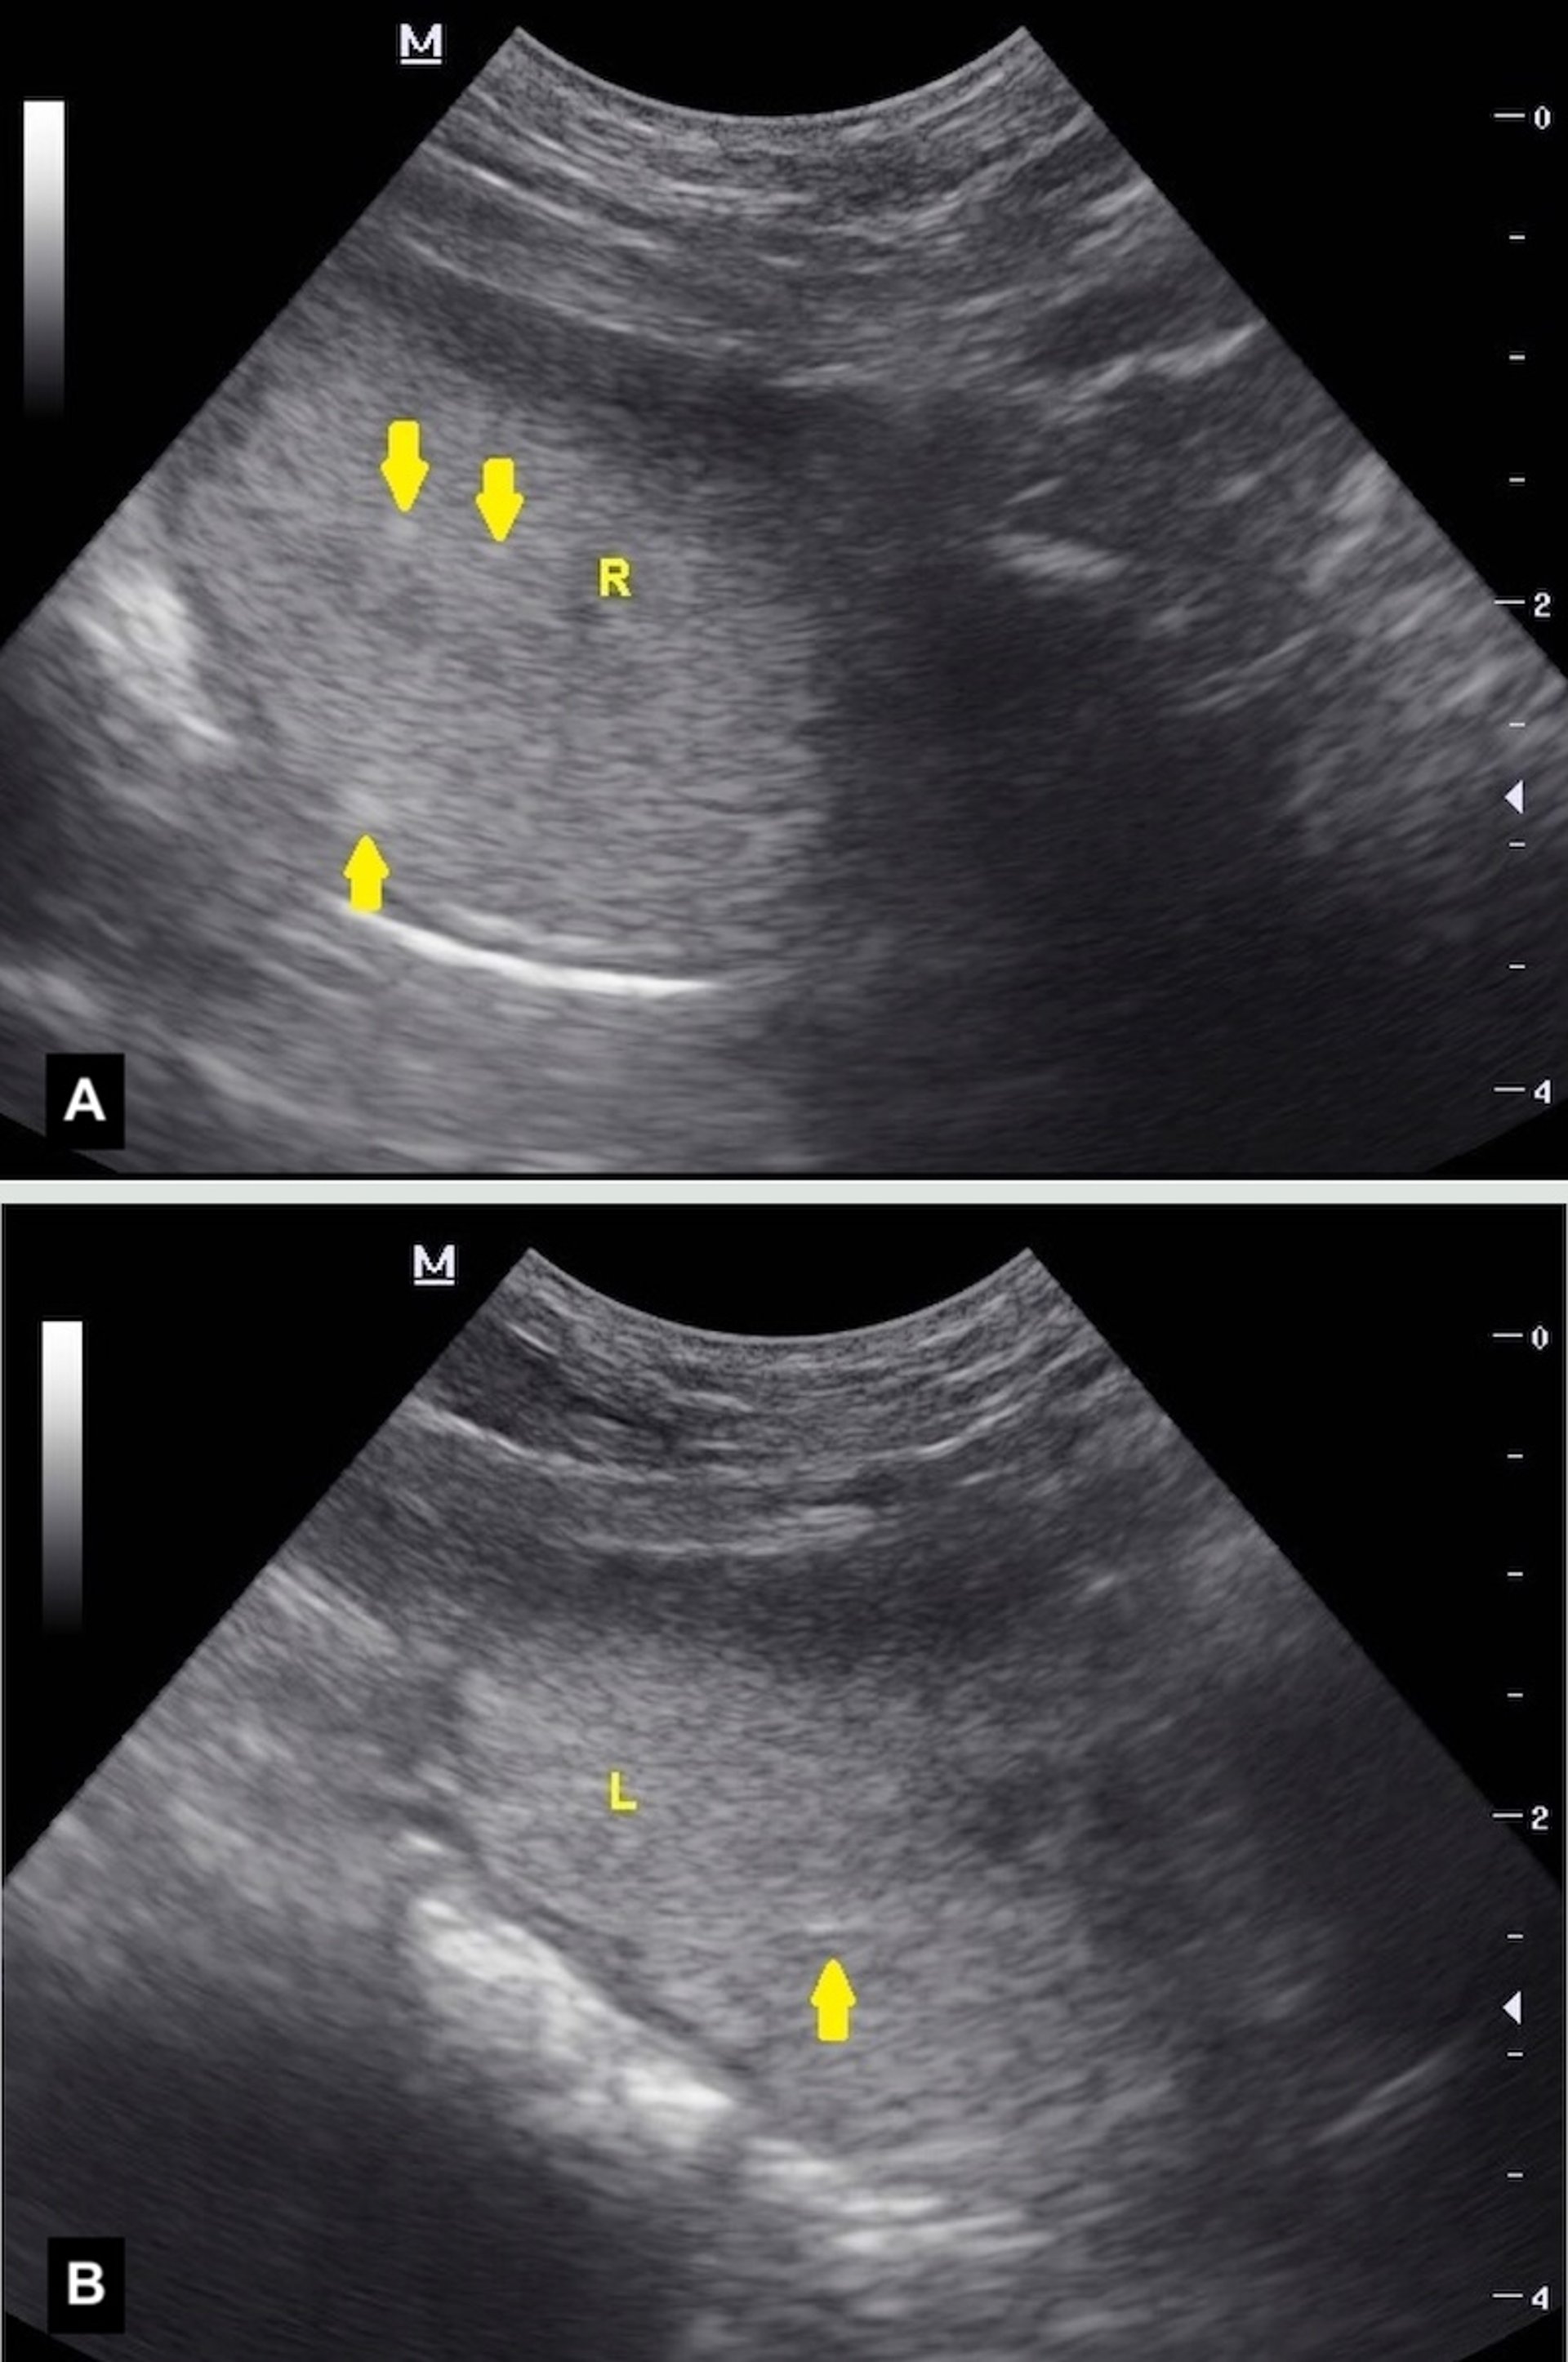

Ultrasonographic views of the parenchyma of the right (A) and left (B) prostatic lobes of a dog with prostatitis. Note the focal to multifocal areas of increased echogenicity (yellow arrows) indicative of prostatic inflammation, which can be associated with benign prostatic hyperplasia, chronic bacterial prostatitis, and prostatic neoplasia.

Courtesy of Dr. Michelle Kutzler.